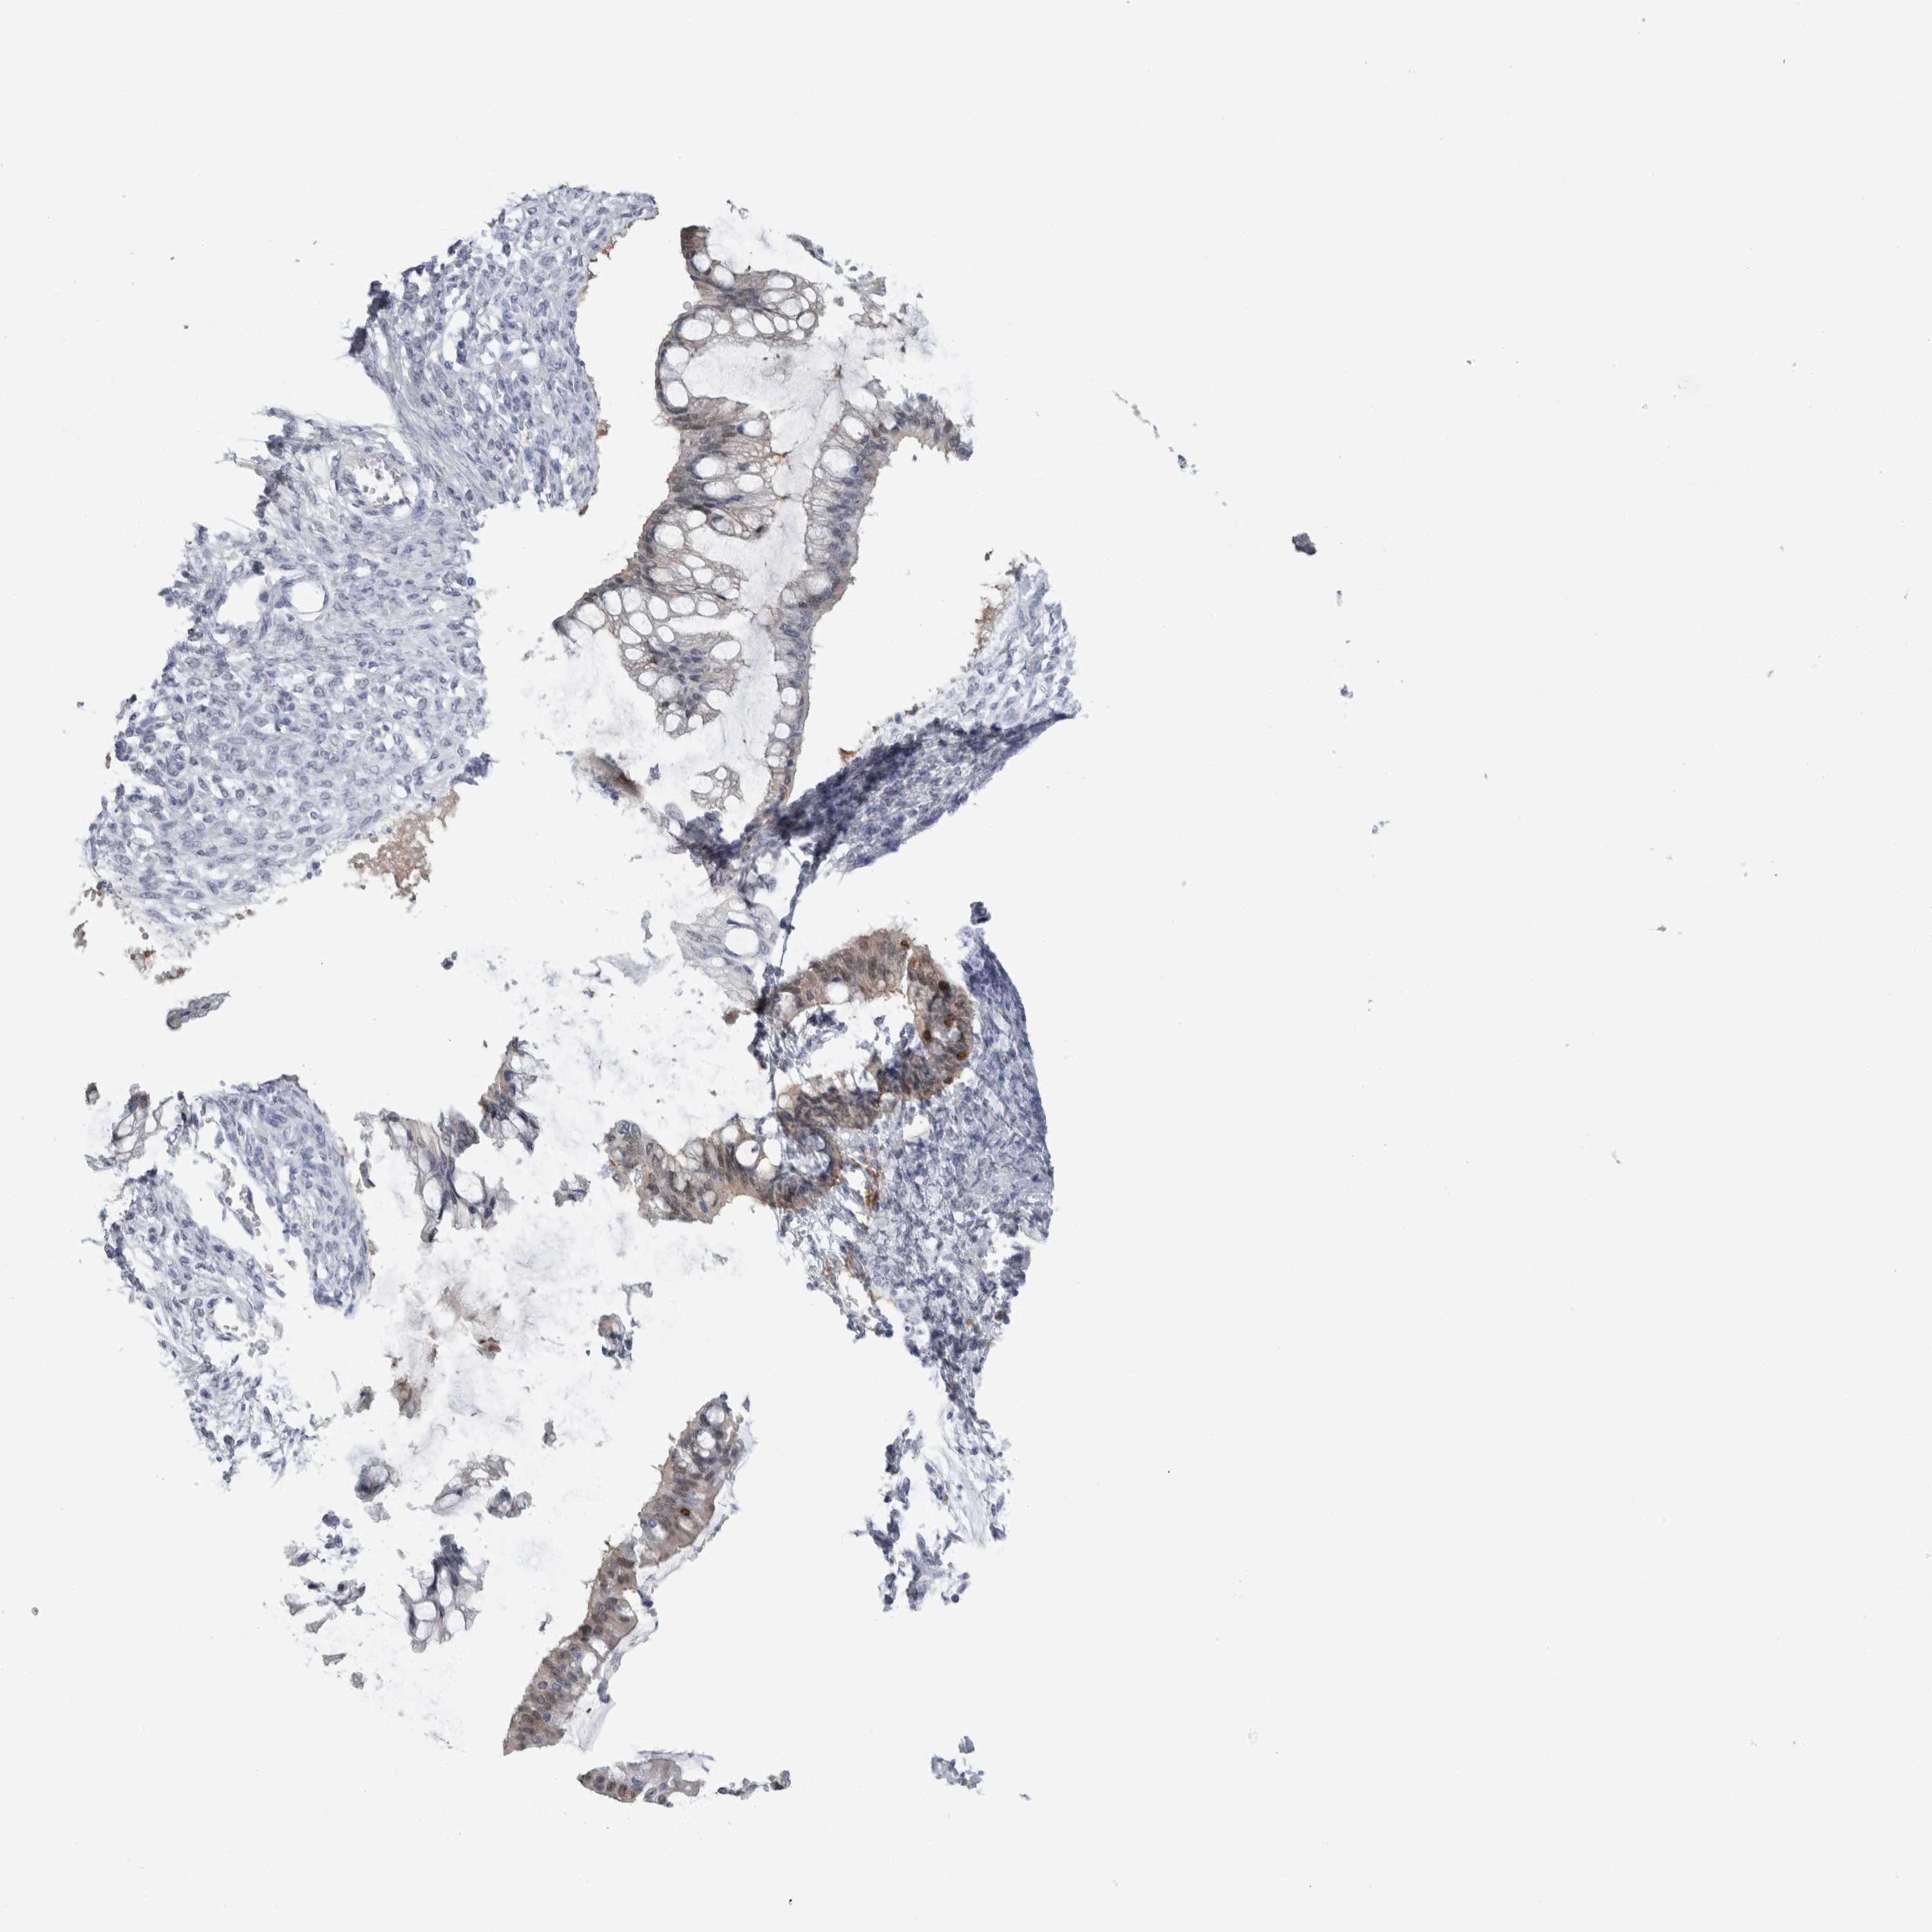

OVARIAN CANCER - Protein expressioni

A mouse-over function shows sample information and annotation data. Click on an image to view it in a full screen mode. Samples can be filtered based on level of antibody staining by selecting one or several of the following categories: high, medium, low and not detected. The assay and annotation is described here.

Note that samples used for immunohistochemistry by the Human Protein Atlas do not correspond to samples in the TCGA dataset.

Antibody stainingi

Antibody staining in the annotated cell types in the current human tissue is reported as not detected, low, medium, or high, based on conventional immunohistochemistry profiling in selected tissues. This score is based on the combination of the staining intensity and fraction of stained cells.

Each image is clickable and will lead to virtual microscopy that enables deeper exploration of all samples and also displays staining intensity scores, fraction scores and subcellular localization as well as patient and tissue information for each sample.

Antibody HPA011337

Antibody HPA024303

Antibody CAB003775

Carcinoma, endometroid

Cystadenocarcinoma, serous, NOS